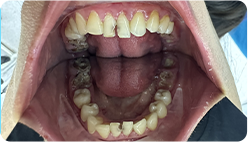

Sau khi chụp X-quang và quan sát trực tiếp,

răng của Ngân đang gặp các vấn đề nghiêm trọng

Hàm trên mất 2 răng do tai nạn giao thông, và 2 năm sau, chân của 2 răng bị lủng, gãy

8 răng bị hư cần điều trị tủy: Răng số 15, 12, 21, 22, 25, 31, 41, 45

Hàm dưới 10 chân răng bị hư nặng, mất chân răng, cần phải nhổ răng số 11, 17, 16, 25, 27, 26, 37, 38, 46, 47